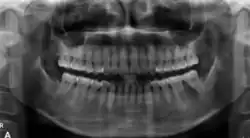

Panoramic radiograph showing a mixed radiopaque-radiolucent lesion around the root of the left first mandibular molar [25]

In its early stages, central ossifying fibroma (COF) appears as a small, well-defined radiolucent lesion due to its fibrous tissue content. Differential diagnoses at this stage include periapical pathology, central giant cell granuloma, and ameloblastoma.[22][23] As the lesion matures, it exhibits a mixed radiolucent-radiopaque appearance due to progressive calcification.[22] At this stage, it should be differentiated from other mixed jaw lesions such as fibrous dysplasia, calcifying epithelial odontogenic tumour, adenomatoid odontogenic tumour, and condensing osteitis.[22] In its mature form, COF may appear predominantly radiopaque, resembling lesions like odontomas, osteoblastomas, or osteosarcomas radiographically.

COF typically presents with well-defined, smooth, and often corticated borders. As a central lesion, it originates within the medullary bone and expands concentrically in all directions.[24] With growth, it may cause tooth displacement, root resorption, inferior displacement of the mandibular canal, and loss or alteration of the lamina dura of adjacent teeth.[25]